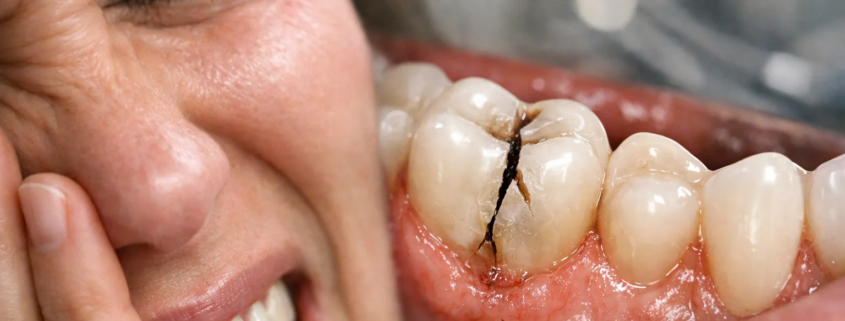

caries sous-jacentes ou parois dentaires affaiblies

À noter : une dent fêlée n’implique pas forcément une “dent cassée” visible.

Comment savoir si c’est vraiment une dent fêlée ?

Le diagnostic se fait au cabinet, car les fissures peuvent être difficiles à voir. Le dentiste peut utiliser :

un examen clinique minutieux + tests de morsure

des tests de sensibilité (froid/chaud)

une évaluation des restaurations existantes